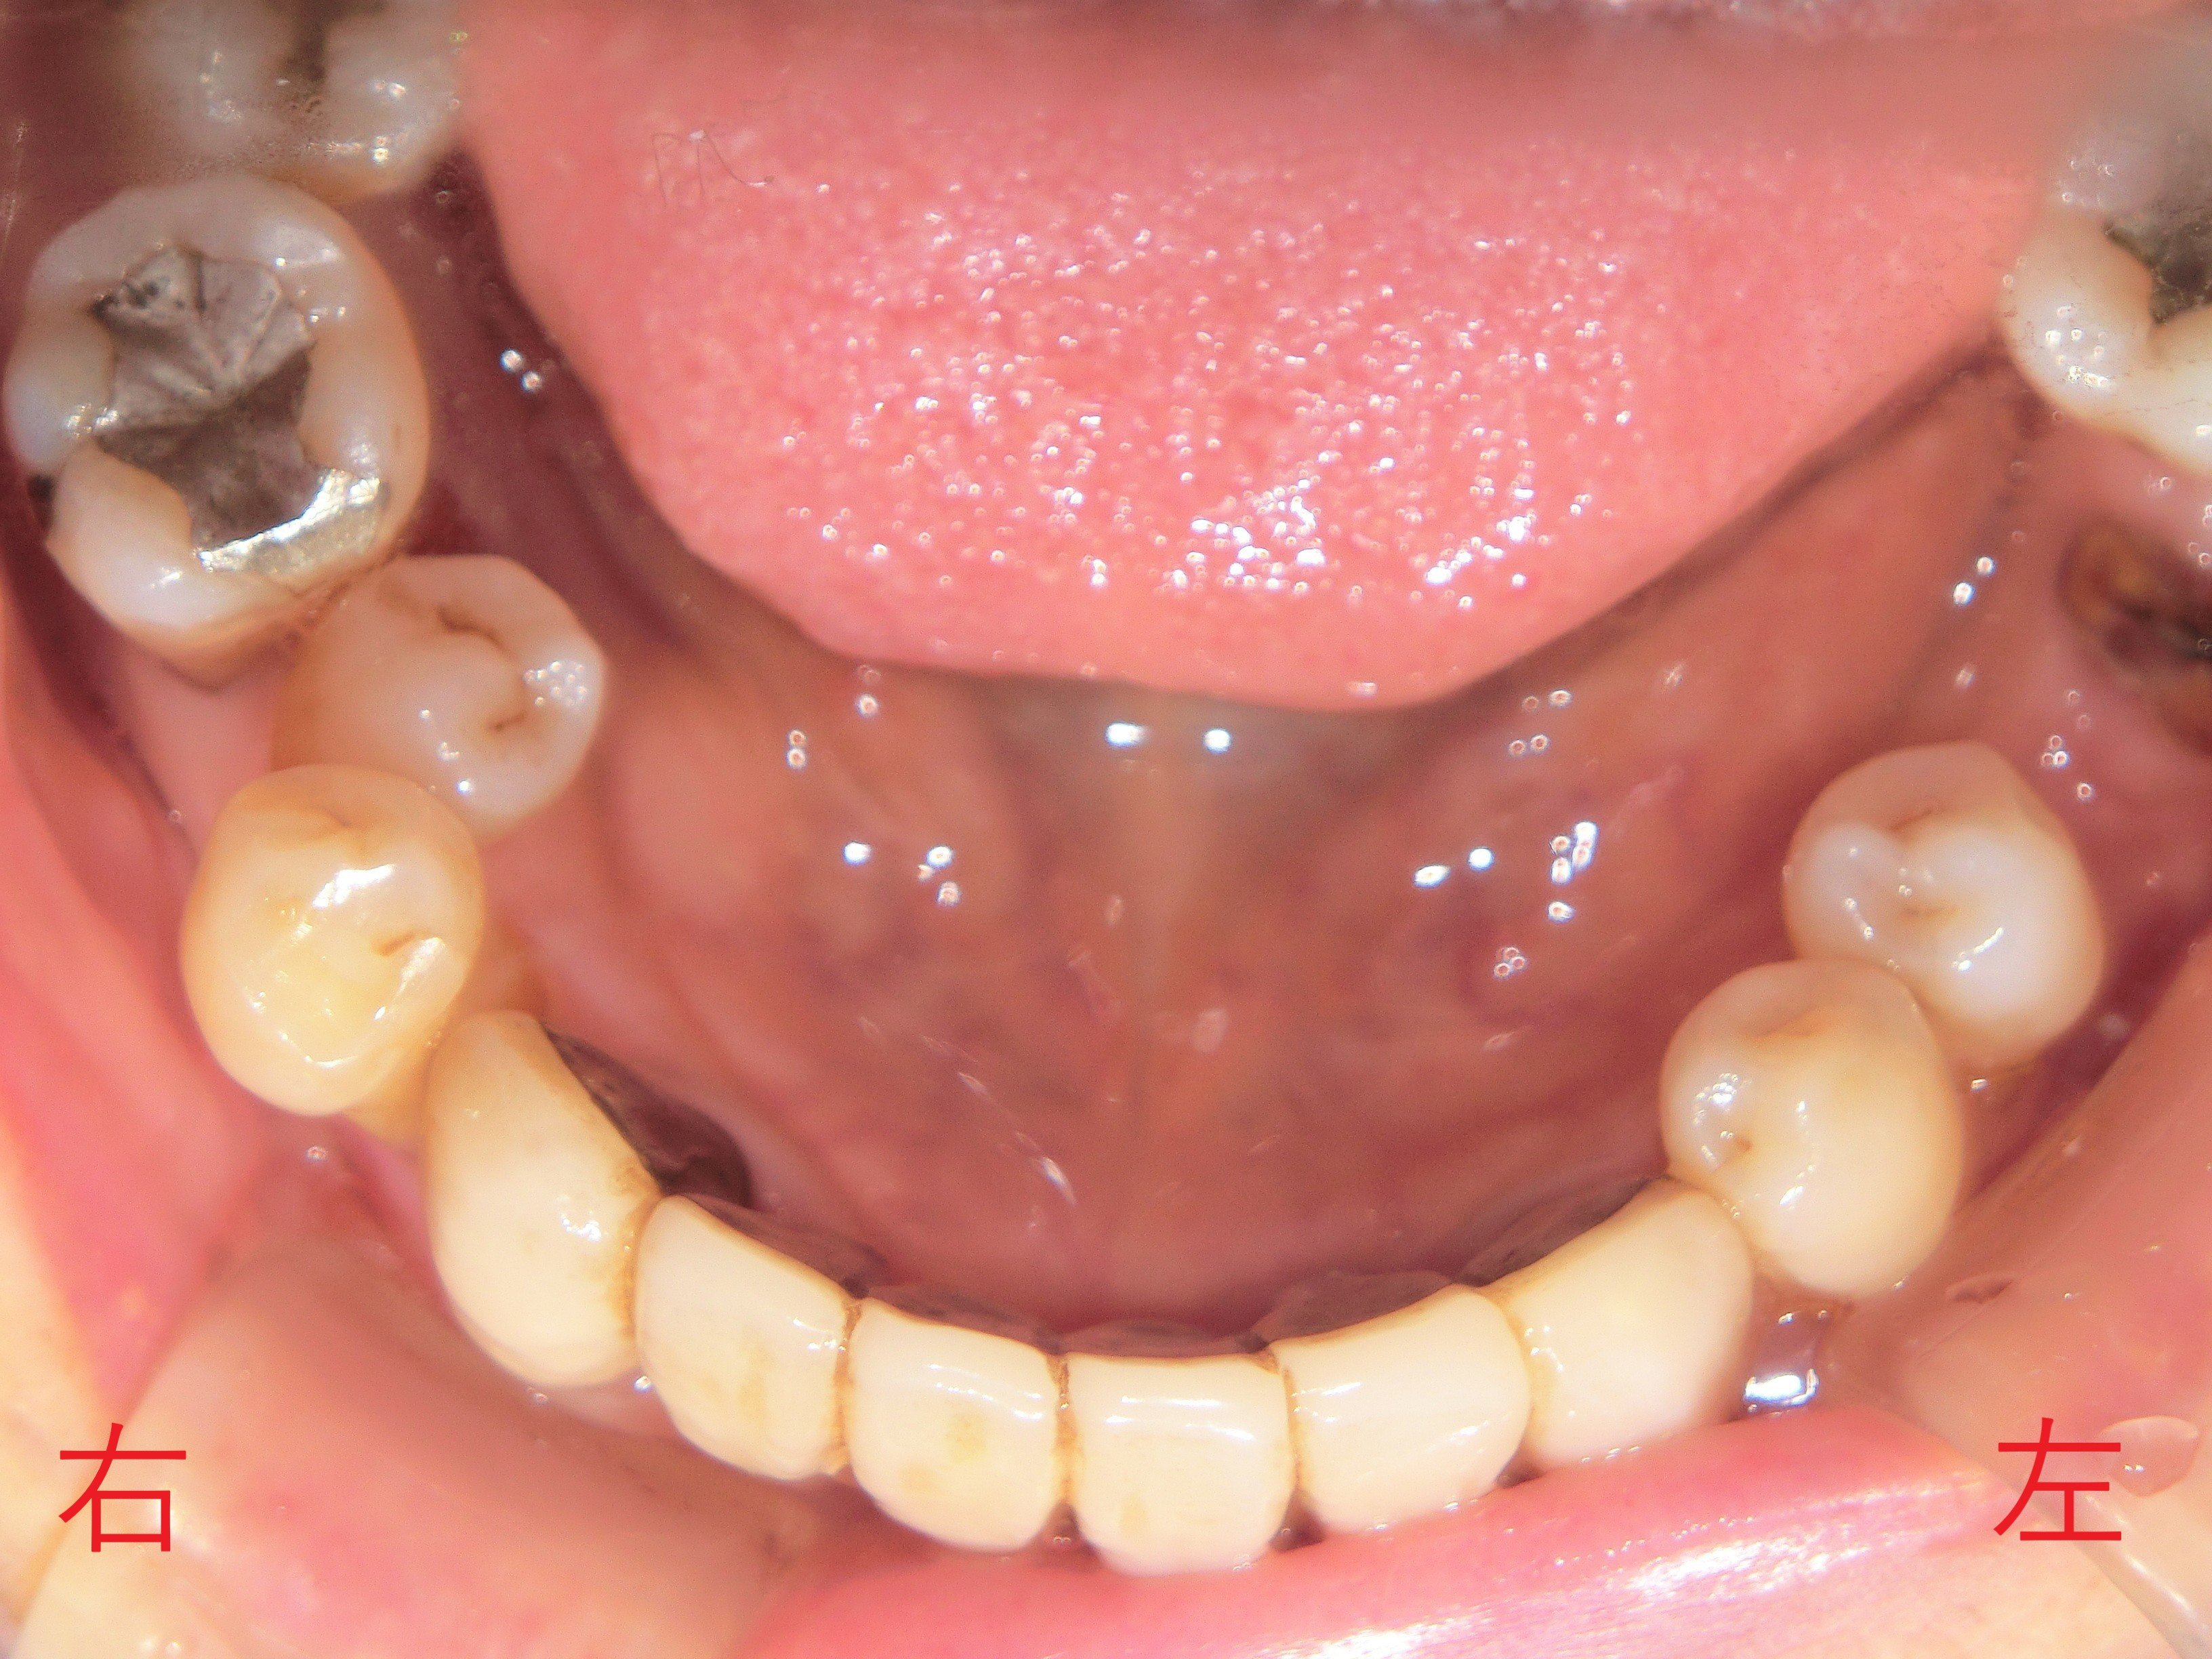

【インプラント埋入と最終補綴】

・上顎に7本、下顎に5本のインプラントを埋入(青色矢印)

・咬合平面の再構築を実施

・一部の天然歯(黄色矢印)は削合・神経除去なしで保存し、咬合関係を確保

・ 被せ物のマージンは清掃性を考慮して歯茎より上に設定

・ 被せ物の色調は写真よりも実際は明るく、患者様も仕上がりに満足されていました